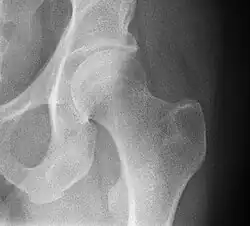

-

Mediale Schenkelhalsfraktur ohne Dislokation -

Laterale Schenkelhalsfraktur mit Adduktions-Dislokation -

Im Vergleich dazu ein gesundes Hüftgelenk